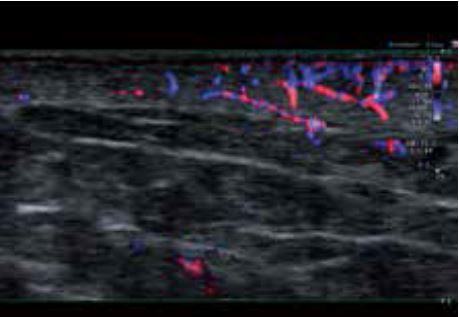

Злоякісна меланома

Під час діагностики меланоми важливо визначити, чи перевищує глибина проникнення ураження 1 мм, оскільки лікування може відрізнятися. Ультрависокочастотний датчик забезпечує безпрецедентну просторову роздільну здатність для візуалізації проникнення ураження під шкіру обличчя ( мал. 3а). Після вимірювання підтверджено, що товщина меланоми трохи перевищує 1 мм. Супермікросудинна візуалізація (SMI), доплерівська технологія, яка здатна відображати низькошвидкісний мікро кровотік, показує велику кількість доплерівських сигналів, що надходять від ураження, підтверджуючи, що це злоякісна меланома (Рис. 3б).

а) Сірошкальне зображення

б) Зображення cSMI

Малюнок 3. Злоякісна меланома, отримана за допомогою PLI-2004BX (24 МГц).